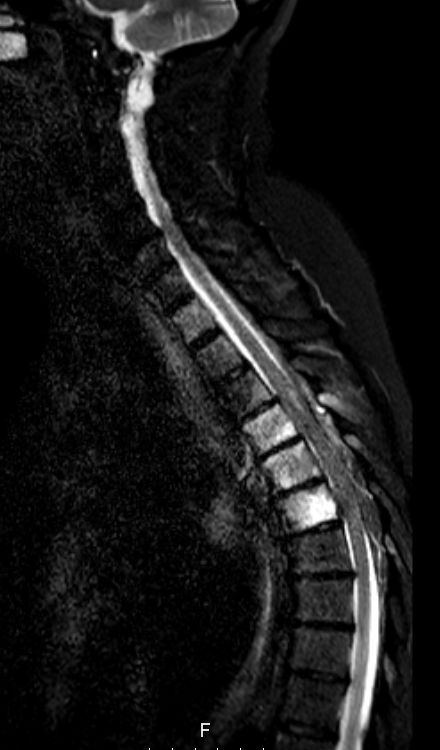

| Rückenmarksmetastasen | 71-jährige Frau mit inkompletter

Querschnittslähmung bei unbekanntem Primärtumor. Knochenbiopsie:

Adenokarzinom. CT: Tumor im linken Lungenoberlappen. Trotz

Notfallbestrahlung Komplettierung der Querschnittslähmung klinisch Th6.![]() |